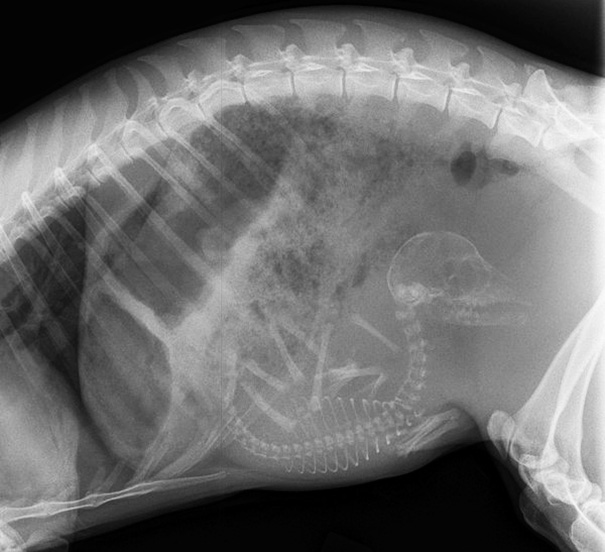

Pregnant Dog X-Ray

These are easier to see then the preg kitten. Looks like a lot of pups in there!

I hope I can't count. There's more puppies then she'll have teats to feed them.

X-Ray Of A Pregnant Dog

An X-Ray Of My Aunt's Pregnant Cocker Spaniel

X-rays are done before the due date to check position of babies and count the number of babies. However is it possible to miscount the babies. Babe, my mom's dog, was bred due to the rarity of her coat color. Everybody prepared for 8-10 puppies. Babe delivered 13 puppies.